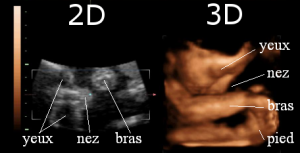

Figure 3 : Echographies 2D (à gauche) et 3D (à droite)

Sur l’échographie 2D de la Figure 3, les membres n’apparaissent pas de manière entièrement visible. Plusieurs images sont nécessaires afin de mieux les analyser et de comprendre les différentes activités du fœtus. À droite, par contre, sur l’échographie 3D, on remarque que le bras, la jambe et les détails du visage (yeux, nez, bouche, oreilles) sont beaucoup plus facilement distinguables. Les articulations également peuvent être repérées sans difficulté. Enfin, grâce à la 3D, certaines malformations cardiaques peuvent être plus rapidement détectées.